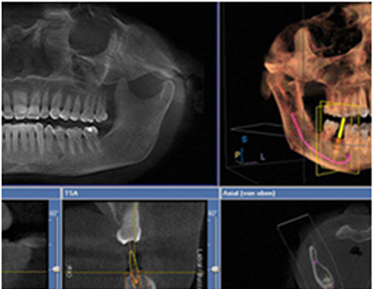

Precise diagnosis with 3D CT

Does not allow even 1mm of error!

Because alveolar bone width, bone density, bone absorption patterns, etc., which cannot be known with 2-dimensional panoramic photos,

can be known, and 3-dimensionally pre-surgical simulation is possible, the accuracy of one-day implant surgery can be increased.